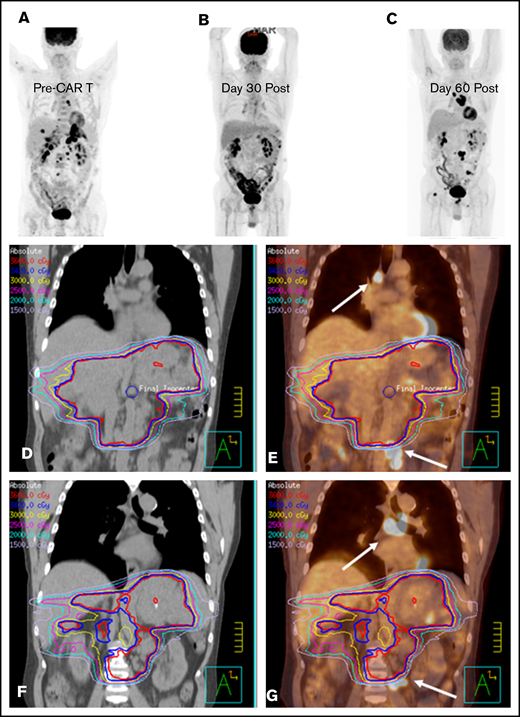

Bridging with a limited RT field in a CAR T-cell patient. (A) PET-CT scout image before CAR T-cell therapy in a male patient with primary refractory DLBCL. He presented 1 month after the illustrated PET-CT scan with severe abdominal pain, prompting CT imaging that revealed increased infiltrative soft tissue masses in the abdomen and pelvis (not shown). (D) Emergent RT was initiated with an intensity-modulated RT (IMRT) plan to the sites of symptomatic disease to an intended dose of 36 Gy; however, only 10.8 Gy was administered. (E) The IMRT plan fused to the sagittal pre–CAR T-cell PET-CT scan illustrates the sites of mediastinal and pelvic disease (arrows) that were excluded from the RT field. (B) The 30-day post–axi-cel PET-CT scan revealed PR to therapy, with a score of 4 on a 5-point scale. The 90-day post–CAR T-cell PET-CT scan (C) revealed new sites of disease progression outside of the RT field, as illustrated by the day-90 CT (F) and PET-CT (G) scans fused to the pre–CAR T-cell RT plan, with the arrows indicating the sites of disease progression outside of the RT field that were present before CAR T-cell therapy.